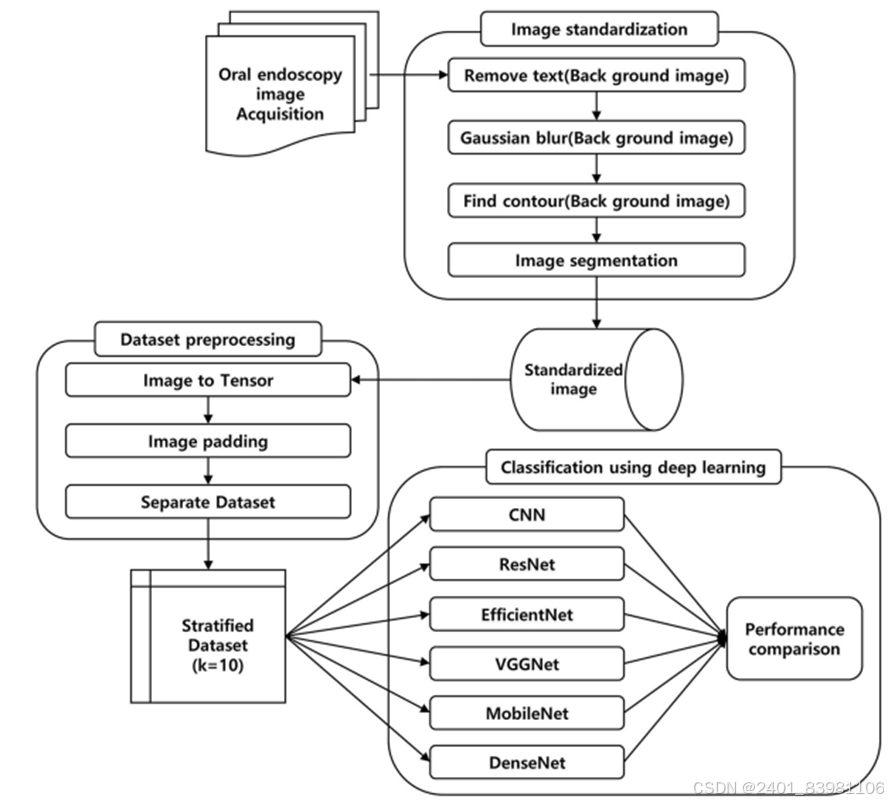

一种基于Resnet50改进的算法流程

采用VGGNET,GradCAM(可以对任意结构的CNN进行可视化),基于创新h-Net模型的中医舌苔苔质分类及其舌苔特征可视化,基于高光谱图像的中医舌苔和舌质分类等

采用VGG时网络优化过程中应用了Dropout策略网络优化策避免过拟合问题但训练样本较少,采集数据困难,训练样本包含舌头外的无关区域等原因,产生的可视化效果并不够完美,仍具有相当大的改进空间

对应的可视化图:

改进的h-Unet架构:

包包括:图像正则化,参数设置(学习率,交叉验证折数)

采用h-Unet解决Unet没有全连接层问题(对应可视化图)

采用VGG时网络优化过程中应用了Dropout策略网络优化策避免过拟合问题但训练样本较少,采集数据困难,训练样本包含舌头外的无关区域等原因,产生的可视化效果并不够完美,仍具有相当大的改进空间